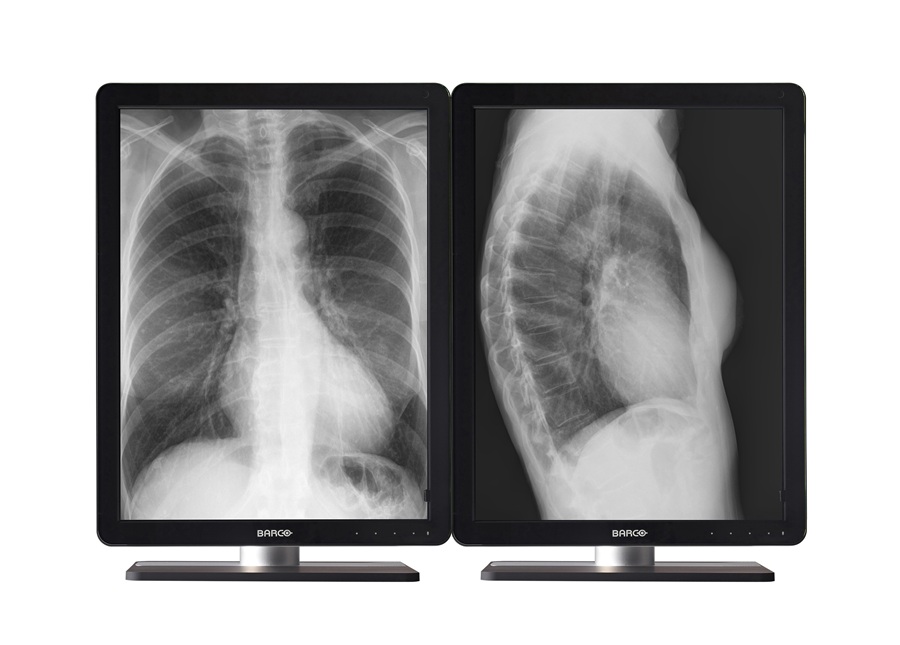

Διαγνωστικές οθόνες υψηλής ευκρίνειας

Οι σύγχρονες εφαρμογές απεικονιστικών ιατρικών διαγνώσεων απαιτούν εξαιρετικής ποιότητας μηχανήματα και οθόνες διάγνωσης, για την απόλυτη απεικόνιση των αποτελεσμάτων.

Η εταιρεία μας προμηθεύει τις υπερυψηλής ευκρίνειας οθόνες για ιατρικά μηχανήματα, της εταιρείας Barco.